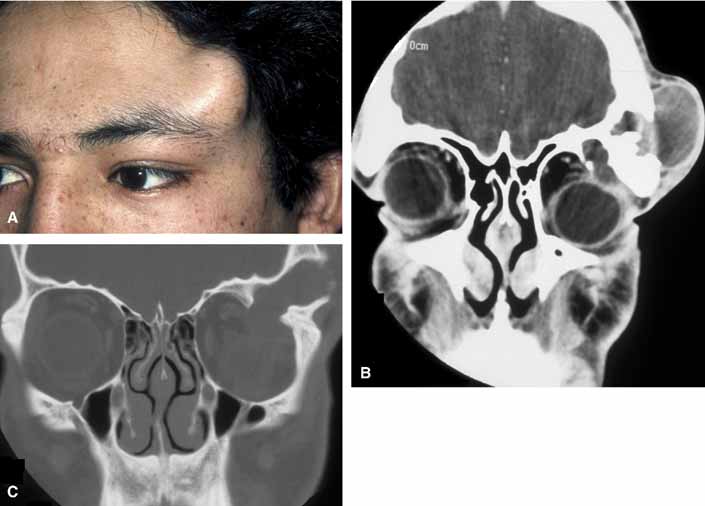

Rarely, an orbital cyst may pass through bony suture lines to extend intracranially or to the temporal fossa (Fig. 2).5,6 Pressure placed on the extracranial portion of a bilobed cyst may be transmitted through the bony dehiscence into the orbit, and is a cause for the mastication proptosis reported by Bullock and Bartley.9

The nature of an orbital dermoid cyst can be demonstrated well by computed tomography (CT): the cyst has a low-density lumen and its relationship to the underlying bone is often manifested by smooth remodeling of the bone secondary to cyst expansion; the high content of fatty material within the cyst makes it radiolucent.

Because of the variable presentation of dermoid cysts, Shields et al.,5 have suggested a classification of orbital dermoid cysts by their association (or lack of association) with suture lines of the skull and assist the clinician in appropriate management. Cysts are classified as juxtasutural, sutural, or soft-tissue dermoid cysts. Those cysts adjacent to the bony suture line but not firmly attached are juxtasutural. A sutural dermoid cyst is firmly attached to bony sutures causing bone erosion, tunnels or an hourglass configuration. Soft tissue dermoid cysts may be strictly confined to soft tissues without any connection to a bone structure. Intradiploic epidermoid cysts are distinctly uncommon and were not included in Shields' classification (Fig. 3).